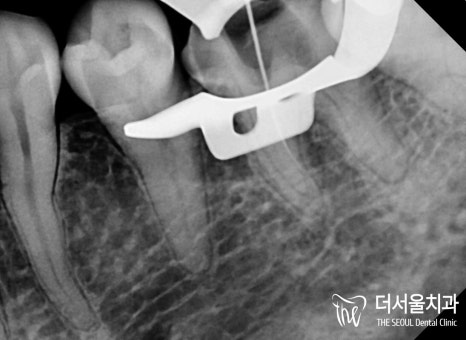

【 개선 후 모습 】

순차적으로 진료를 진행하여

감염된 곳을 깨끗하게 청소하고

밀폐, 소독, 충전을 진행했습니다.

재신경치료는 성공률이

매우 낮은 편에 속하기 때문에

의료진의 실력, 꼼꼼한 과정

모든 게 중요하다 할 수 있는데요.

놓치는 부분이 없도록

재차 확인을 거쳐

과정을 마칠 수 있었습니다.